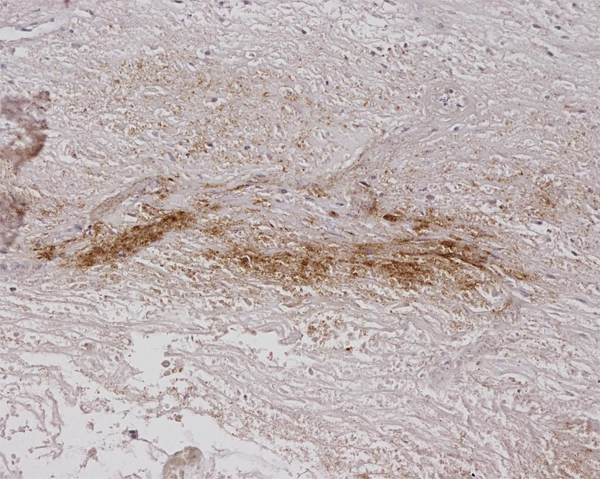

IHC (Immunohistochemistry)

(Immunohistochemistry analysis using Mouse Anti-Alginate Monoclonal Antibody, Clone 4B10-1C5. Tissue: Burned Skin. Species: Human. Primary Antibody: Mouse Anti-Alginate Monoclonal Antibody at 1:200.)